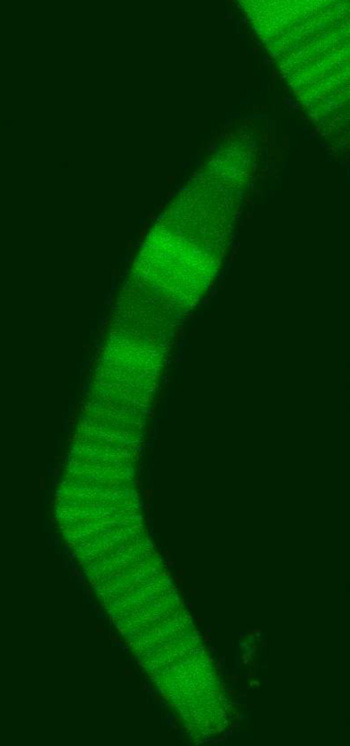

| SUNY Cortland Assistant Professor of Physics Aphrodite Ahmadi's study encompassed the basics of eye rod flexibility. This genetically fragile rod is shown bending as it begins to fail. The above left image, which details the rods bending, appeared in the Biophysical Journal and is reproduced here with the journal's permission. |

When looked at under a microscope, the rod photoreceptor cells in a tadpole eye appeared to gradually bend into a crook like a boomerang and break. Eventually, the rods no longer will transfer visual information to the brain.

"We did this study to see how this bending and breakage depends on the concentration of rhodopsin along the cell,” she said. “In regions with higher concentration of rhodopsin the rod becomes less flexible and will break under pressure.”

“Some graphs compare high density versus low density bends,” Ahmadi said. “The normal cell recovers its structure, but in a high density band it keeps bending and bending because it has lost its internal structure.”